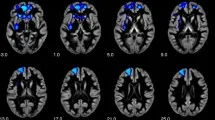

FA положительно коррелировала с PNI total в правом заднем cingulum и PNI Vulnerable в левом переднем cingulum и правом заднем cingulum. Более detailed information о location и cluster size представлена в табличных данных. Результаты представлены графически на рисунках.

Не было обнаружено significant correlations для PNI Grandiosity. Дополнительные exploratory analyses подшкал выявили positive correlations FA и DEV (devaluing) в двух кластерах в левом переднем cingulum. Кроме того, другой positive effect был найден для FA и ENTR (entitlement rage) в левом переднем cingulum.

Одна prominent feature фронтолимбических сетей - их relation к emotion regulation, которая является core feature нарциссизма и была emphasized в previous imaging studies. Наши findings предполагают positive association FA в dorsolimbic areas (левый передний и правый задний cingulum) и уязвимых нарциссических чертах.

Эти результаты могут быть interpreted как demand управления negative feelings такими как anger, rage, и shame, которые ассоциированы с narcissistic vulnerability. Более precisely, anterior sections предполагаются referring к emotional appraisal (connections к amygdala и orbitofrontal cortex - OFC) и могли бы объяснить наши significant correlations с подшкалами entitlement rage и devaluing.